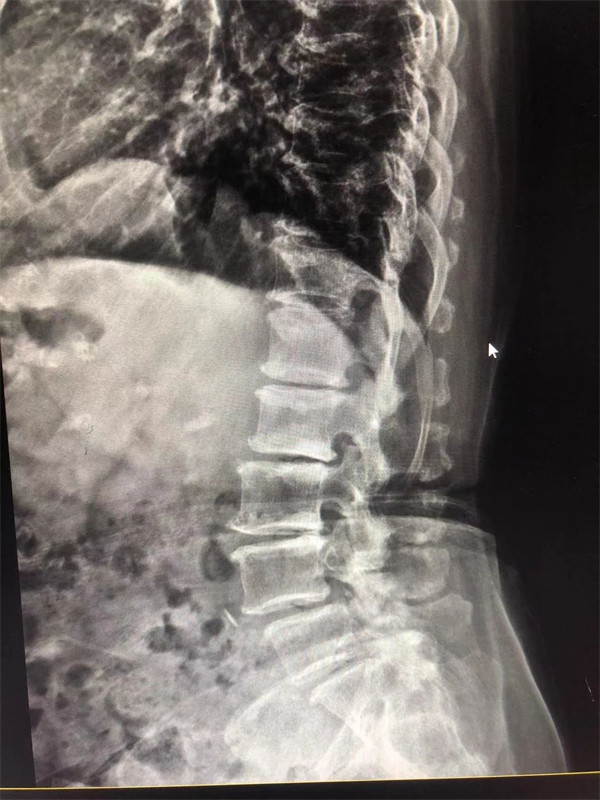

手術(shù)前↓

戈主任仔細詢問阿婆病情癥狀,綜合查體及MRI片情況,認為阿婆有明顯的腰椎滑脫,腰椎管狹窄,這是引發(fā)阿婆病痛的主要因素。

阿婆曾在院外多家醫(yī)院就醫(yī),被診斷為腰4椎體滑脫癥、腰椎管狹窄癥、腰椎間盤突出癥,外院予以止痛、理療、針灸等各種保守方式治療,病情未見明顯改善。